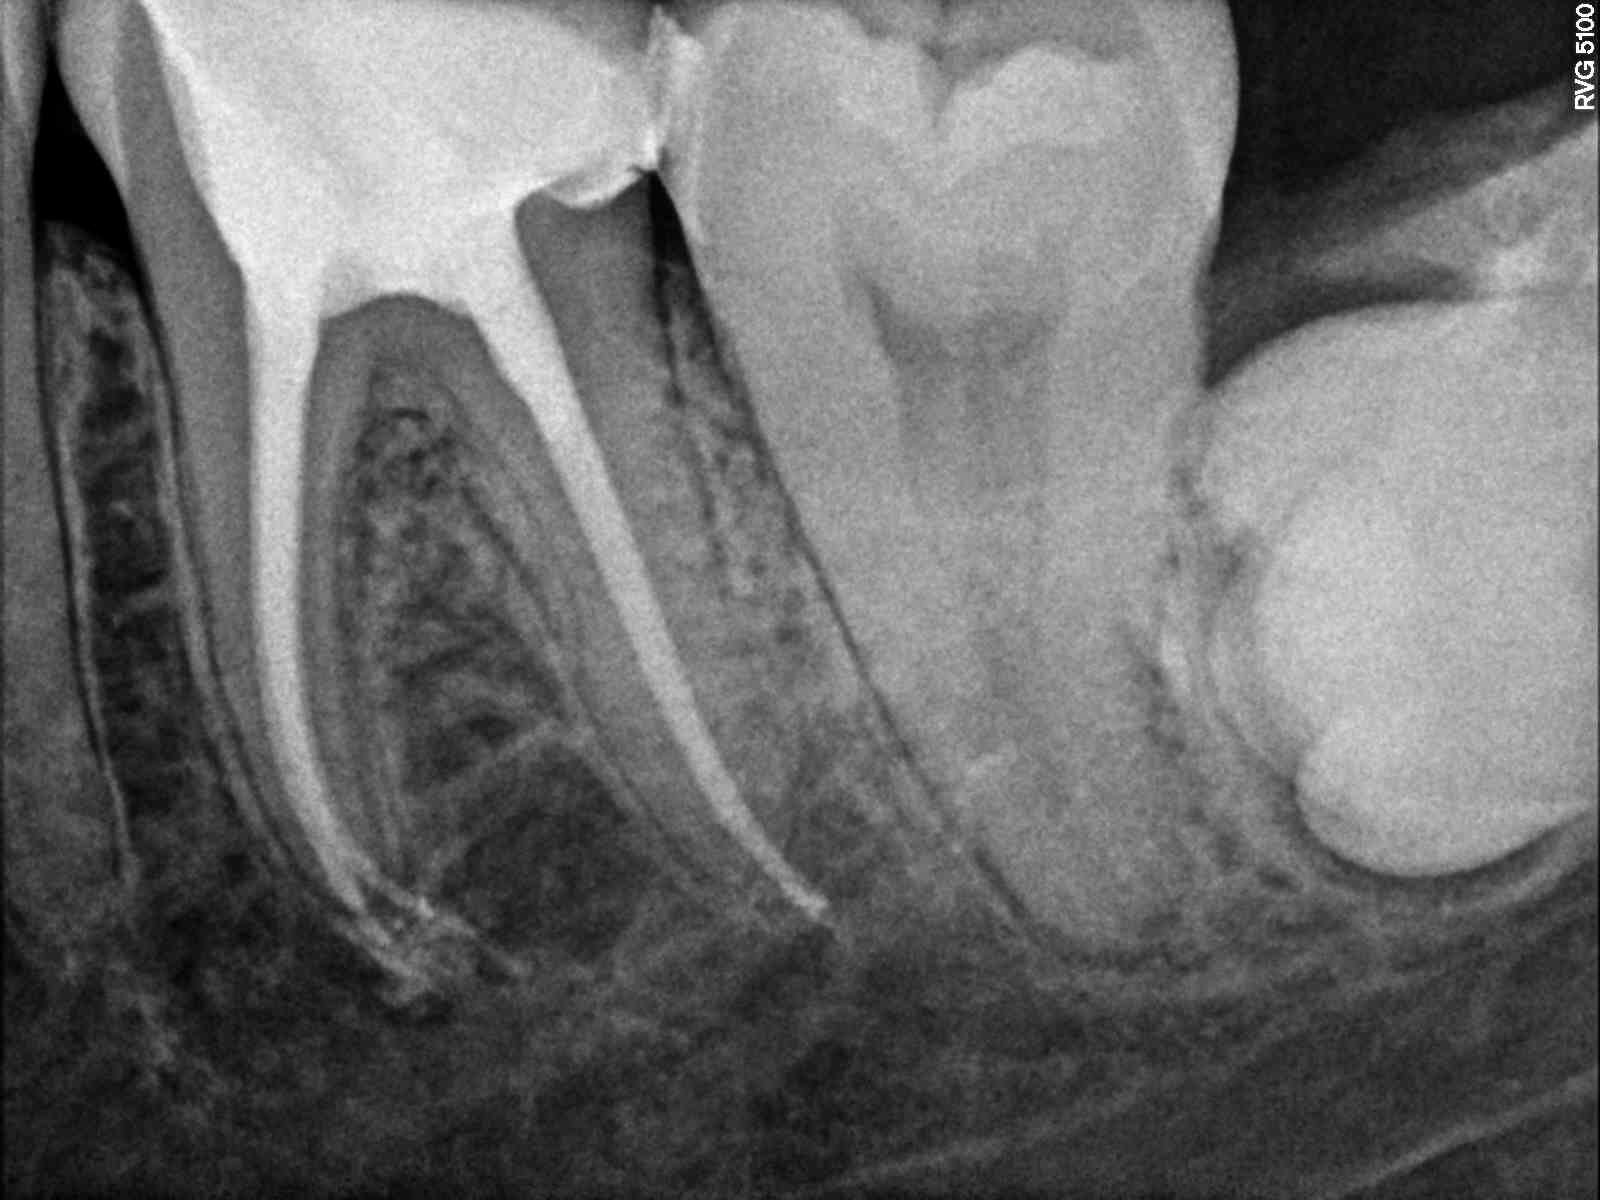

Et un trait de fracture à mi-hauteur de la ou des racines M, sur les radios 2 et 3, avant et après l'inlay-core?

c'est ce que je vois aussi et l'épaississement en mésial visible sur la dernière radio fait suite à ce trait.

mais comment en être sûr à 100% ?

Dépose de l'inlay core et microscope.